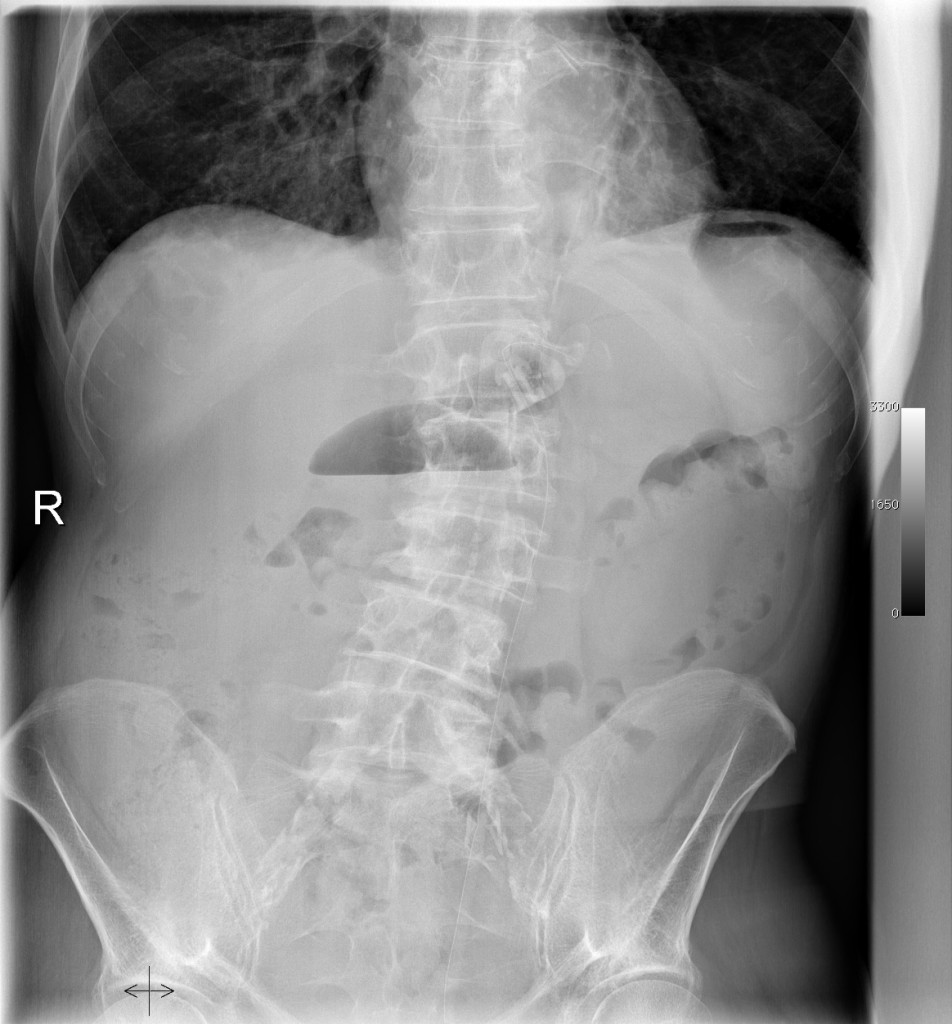

Xray Abdomen Ileus Medical Doctors Stock Photo Image of doctors What Is The Medical Definition For Ileus ileus is a temporary lack of the normal muscle contractions of the intestines. ileus is a temporary lack of movement in the intestines that can lead to pain,. ileus is a slowing of gastrointestinal motility that is not associated with mechanical obstruction. ileus is a temporary arrest of intestinal peristalsis. Abdominal surgery and medications that. . What Is The Medical Definition For Ileus.